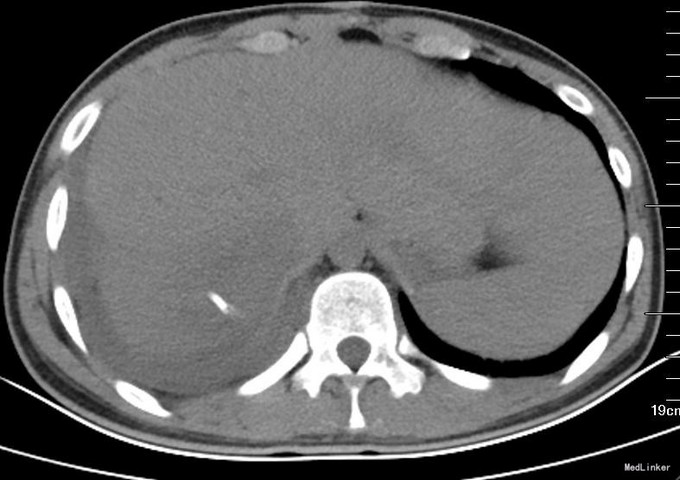

患者术前CT因为外院检查,未得以资料。介入术后17天复查CT(图1):可见引流管留置,肝右后叶占位,6*4cm,实性为主。术后2个月行肝脏增强CT复查(图2):肝右后叶病变,液性区域不多。术后5个月再次行MRI(图3):肝右后叶占位,实性部分占大部分,且与其他肝脏各段似有分界。考虑穿刺引流不能达到消除病灶。行外科手术治疗。手术方案为:肝部分切除,完整切除占位(图4)送冰冻病理回报:炎性假瘤,伴肉芽肿病变。术后患者恢复良好,出院。石蜡病理:考虑结核。